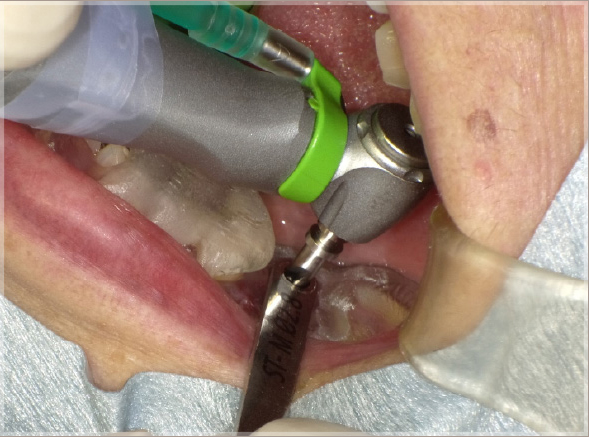

1.折れた歯を抜歯します

①破折線確認

②抜歯